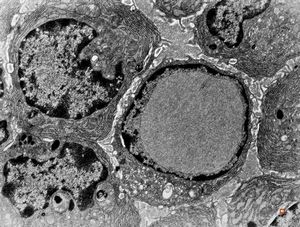

M, | intranuclear inclusion - plasmocyte, tonsilla palatina